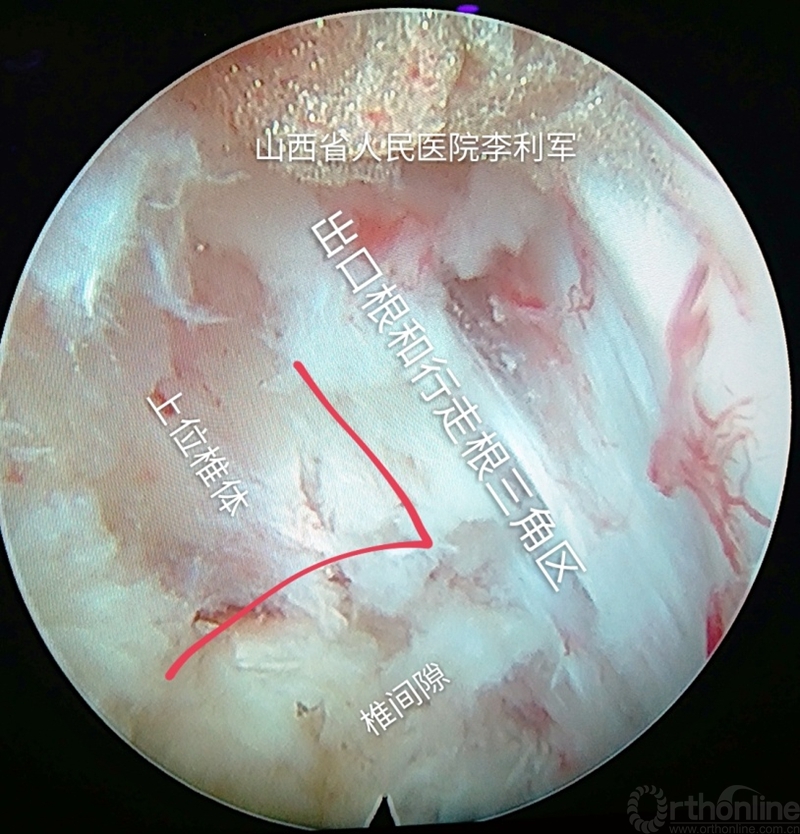

第六步:逐步调整和旋转通道,移向出口根和行走根交叉的三角区,做此处减压,根据具体情况可以再重复上述成型的过程去除阻挡的关节突,达到这个部位的减压。如图13-14

图13 逐步调整通道做出口根和行走根三角区减压

图14 逐步调整通道做出口根和行走根三角区减压